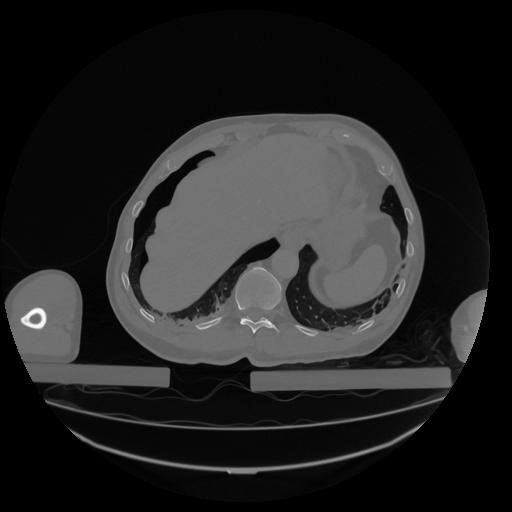

34 CUERPO,CE,Vol,1.0,CUERPO,,